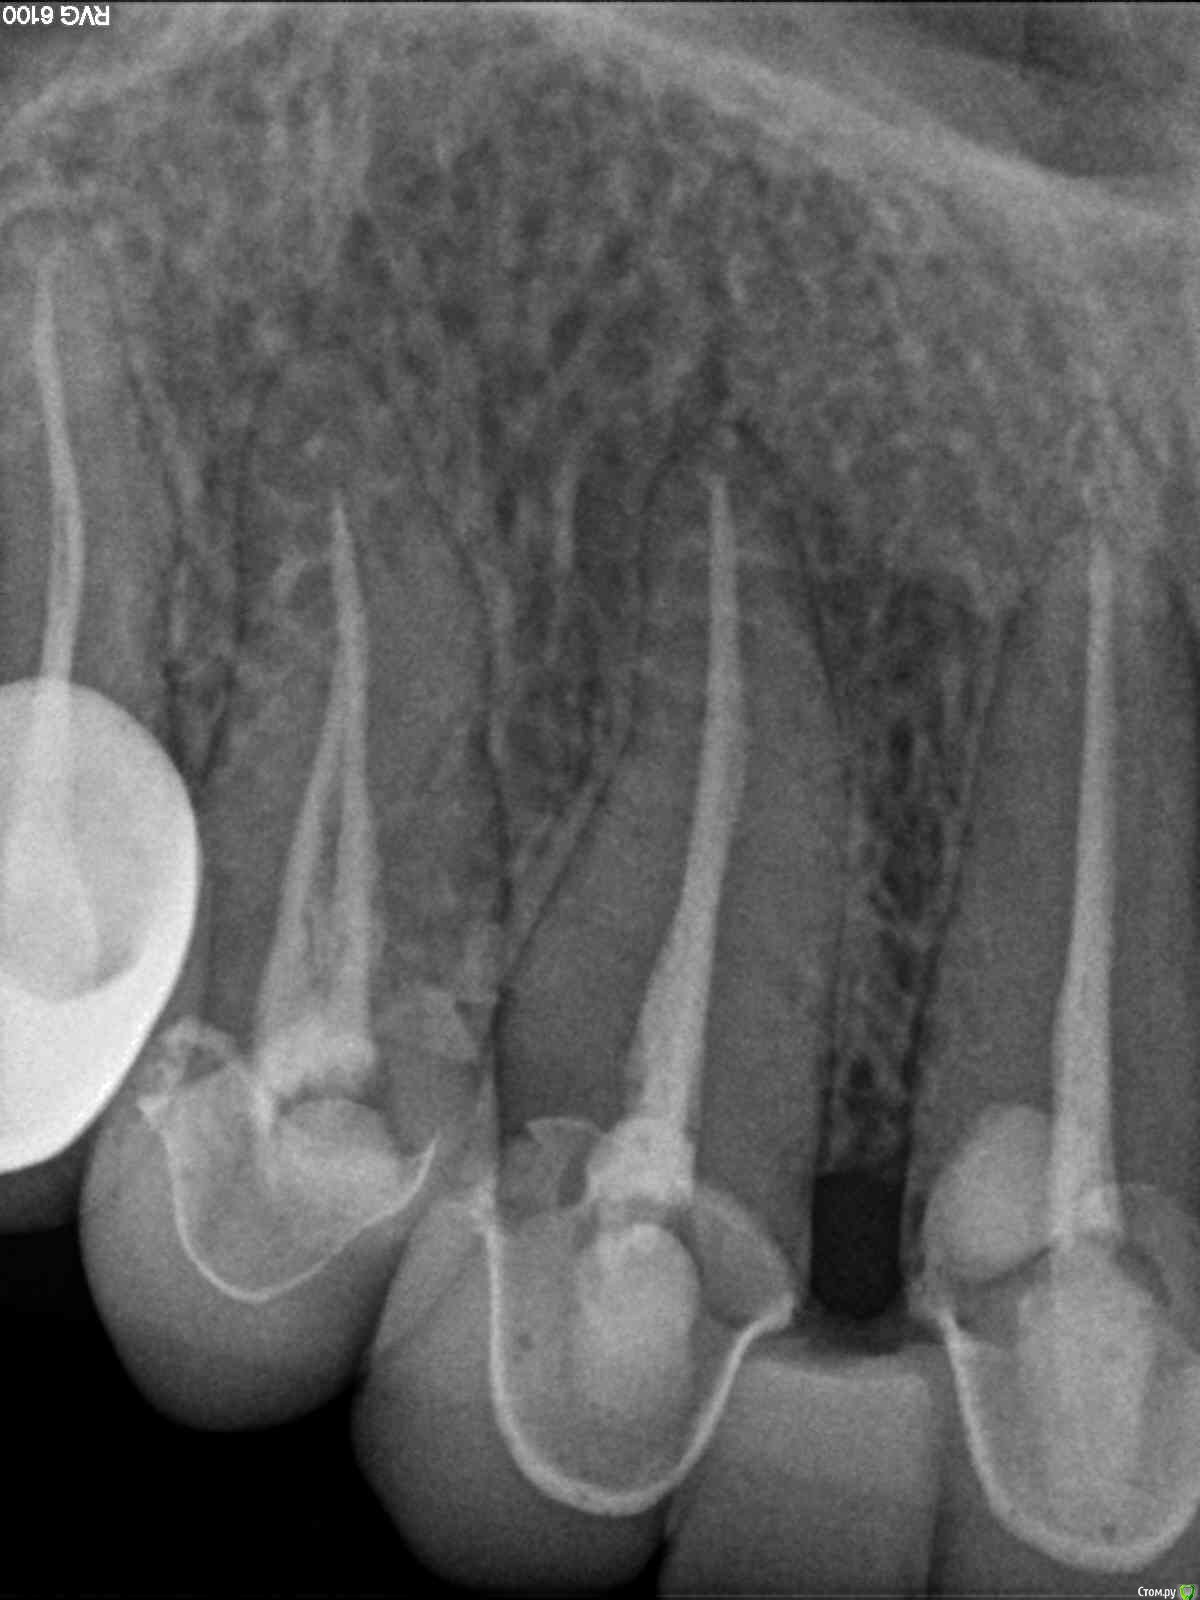

lazzal Опубликовано 29 октября, 2015 Поделиться Опубликовано 29 октября, 2015 (изменено) Уважаемые ортопеды, дайте пожалуйста совет и свои рекомендации. в 2012 г была установлена конструкция на передние верхние зубы из безметалловой керамики. 2 мини моста резец-клык справа и слева. устанавливались на свои абсолютно здоровые зубы, предварительно депульпированные, так сделать предложил врач, чтоб была типа "голливудская улыбка". у меня от природы отсутствовали двойки с обоих сторон, правда зазор был не большой, но все равно смотрелось не очень, клыки сразу бросались в глаза. так вот, врач мне сказал, что конструкция прослужит 20 лет, а у меня через 2,5 года начались проблемы. начали чернеть кромки вдоль конструкции с внутренней стороны. терапевт диагностировал кариес. ортопед сказал снимать не надо, можно их изнутри немного сточить, пролечить кариес и запломбировать. так и сделала. но пломбы теперь вылетают каждые 3-4 месяца. врач который лечит, сделал снимки и сказал, что там с правой стороны между резцом и клыком гниет корень и надо конструкцию снимать, а то потеряем корень. мой ортопед же говорит, что все нормально - пусть стоят, надо лучше пломбировать. снимать я сама не хочу конечно. но корень дороже. кто из них прав и что мне делать? еще сложность в том, что конструкция похоже крепится на какой-то супер клей и просто так ее сбить или спилить не получится (проговорился мой ортопед). я не представляю как это все может выглядеть, стешут по самые десны и сделают вкладки? очень бы этого не хотелось, т.к. хотелось бы этот вариант оставить про запас, т.к. потом, если что случись - олько имплантация и то, если это будет возможно. Посмотрите снимки и подскажите, что можно сделать им почему такой короткий срок службы? как смог развиться кариес? Так же прилагаю и панорамный снимок, возможно вы увидите и укажете мне на еще какие-то проблемы с зубами или деснами, на которые стоит обратить внимание. С уважением и благодарностью, я. Изменено 29 октября, 2015 пользователем lazzal Ссылка на комментарий

lazzal Опубликовано 30 октября, 2015 Автор Поделиться Опубликовано 30 октября, 2015 Посмотрите пожалуйста в каком состоянии зуб под коронкой, возможно ли его спасти? Ссылка на комментарий

Bier Опубликовано 30 октября, 2015 Поделиться Опубликовано 30 октября, 2015 В плачевном состоянии, его сохранение под вопросом 1 Ссылка на комментарий